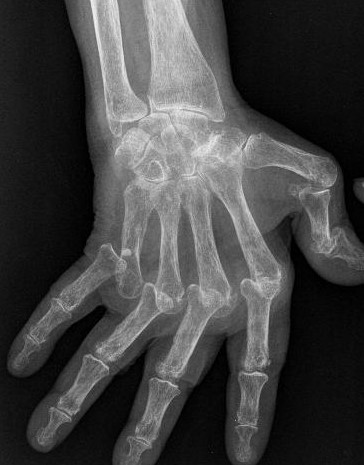

O osso é envolvido com aparecimento de erosões ósseas (visíveis ao rx) (ver figura 2 e 3) e que podem confluir e atingir grandes proporções). A presença de osteopenia é característica nos casos moderadamente avançados e nos doentes submetidos a longos períodos de terapia com corticoesteroides.

O LES manifesta-se de forma algo diferente. As erosões ósseas características da AR ocorrem de forma muito menos exuberante, ou estão ausentes. Por outro lado, afetam de forma muito mais intensa as estruturas capsulo-ligamentares, provocando-lhe grande laxidez e consequentemente sub-luxações e luxações. (ver figuras 4 e 5)